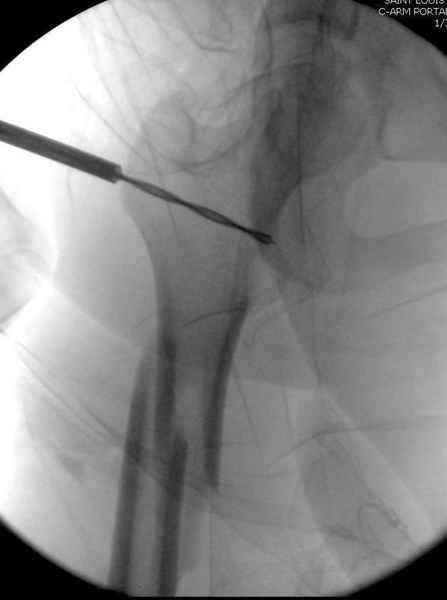

Больной долго оставался нестабильным, только на 14 день удалось заменить на антеградный интромедуллярный штифт TFN (trochanteric femoral nail) SmithNephew. После неудачной попытки закрытой репозиции, несмотря на использование "joystick", проксимальный стержень от

наружного фиксатора, (перелом начал срастаться) репозицию провели из малого доступа, затем остальные этапы операции.

Случай был представлен из-за того, что больного оперировали после наружной фиксации и был риск инфекцирования через места проведения стержней (на снимках), прошло больше 3 месяцев, выписан из амбулаторной службы из-за отсутсвия надобности дальнейшего наблюдения.